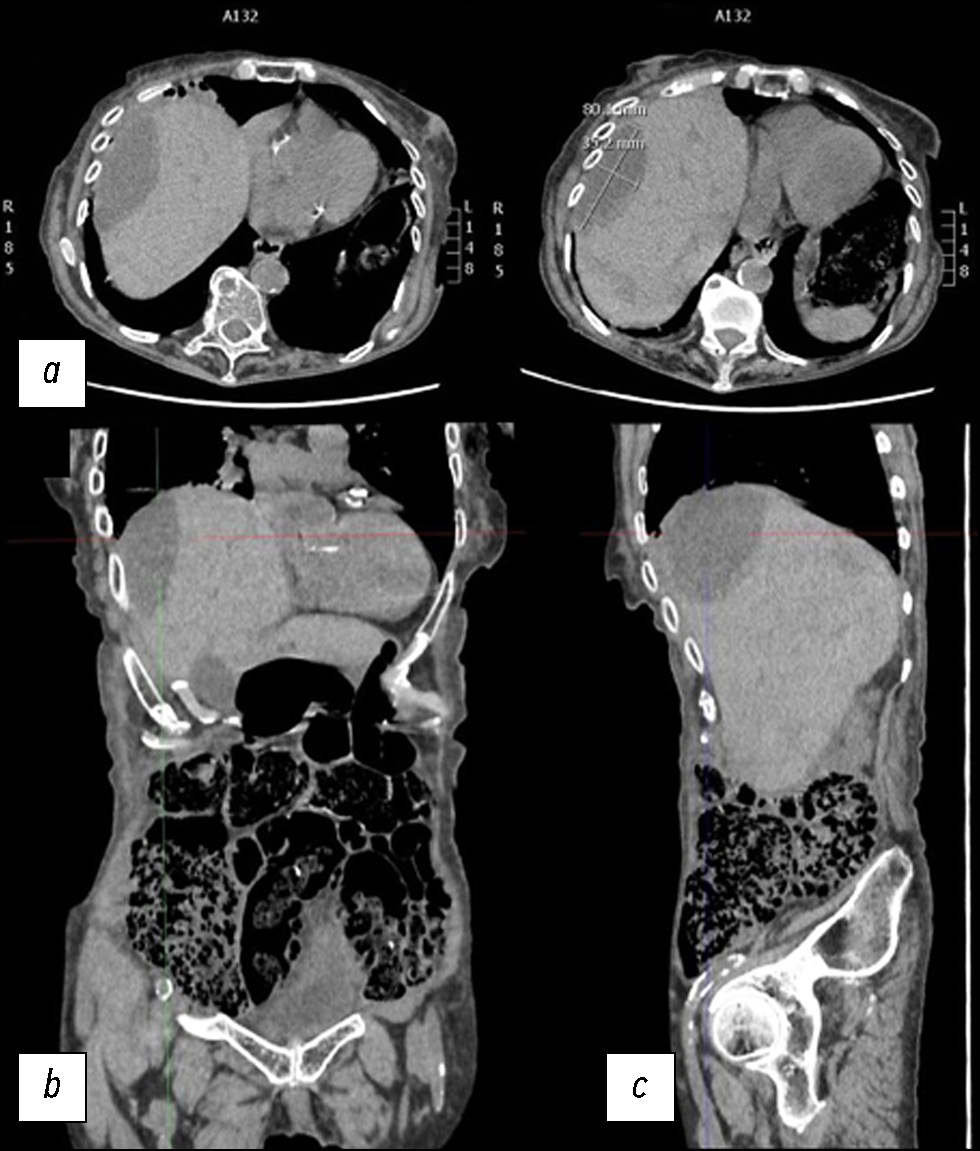

自发性肝破裂病例及影像学的作用:从计算机断层扫描到干预治疗

肝实质破裂是一种罕见但可能致命的疾病,可由外伤、医源性因素、自发性原因等引起。 本文通过一个病例报告,介绍了在治疗一名自发性肝实质破裂患者时所采用的诊断和治疗措施。一名老年妇女因弥漫性腹痛被送入急诊科。临床检查后,她接受了计算机断层扫描。第一次计算机断层扫描的结果并未发现全面的实质破裂。由于腹痛可能由肾绞痛或胆绞痛引起,已知信息模糊,因此早期诊断非常困难。在肝实质中只发现了几个椭圆形低密度肿块,肿块内充满了密度增高的液体。然而,疼痛持续了数天,由于患者病情恶化,进行了补充的放射检查,结果显示肝实质破裂。因此有必要进一步进行动脉造影,并延长住院时间,直到临床症状缓解。